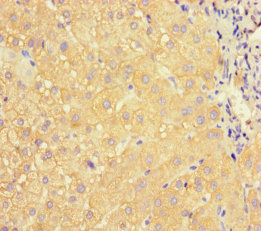

Immunohistochemistry of paraffin-embedded human liver tissue using CSB-PA12197A0Rb at dilution of 1:100